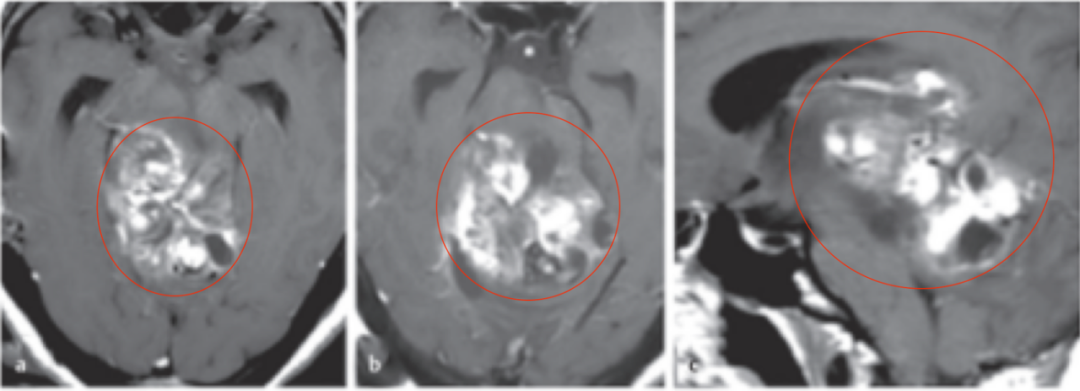

图:术前MR检查,轴位、矢状位MR显示巨大脑干肿瘤占位,信号不一,从中脑两侧延伸压迫到丘脑、脑桥和小脑。

放疗、长达12个月的化疗……肿瘤不仅没有被控制,反而像滴在宣纸上的墨渍,悄然晕染、扩散,从中脑蔓延至丘脑、脑桥、小脑,威胁着她的生命。

当艾米丽不远千里,终于坐在巴特朗菲教授面前时,肿瘤已经发展到了非常严重的阶段。巴教授在详细评估病情后,建议进行广泛的肿瘤切除手术。